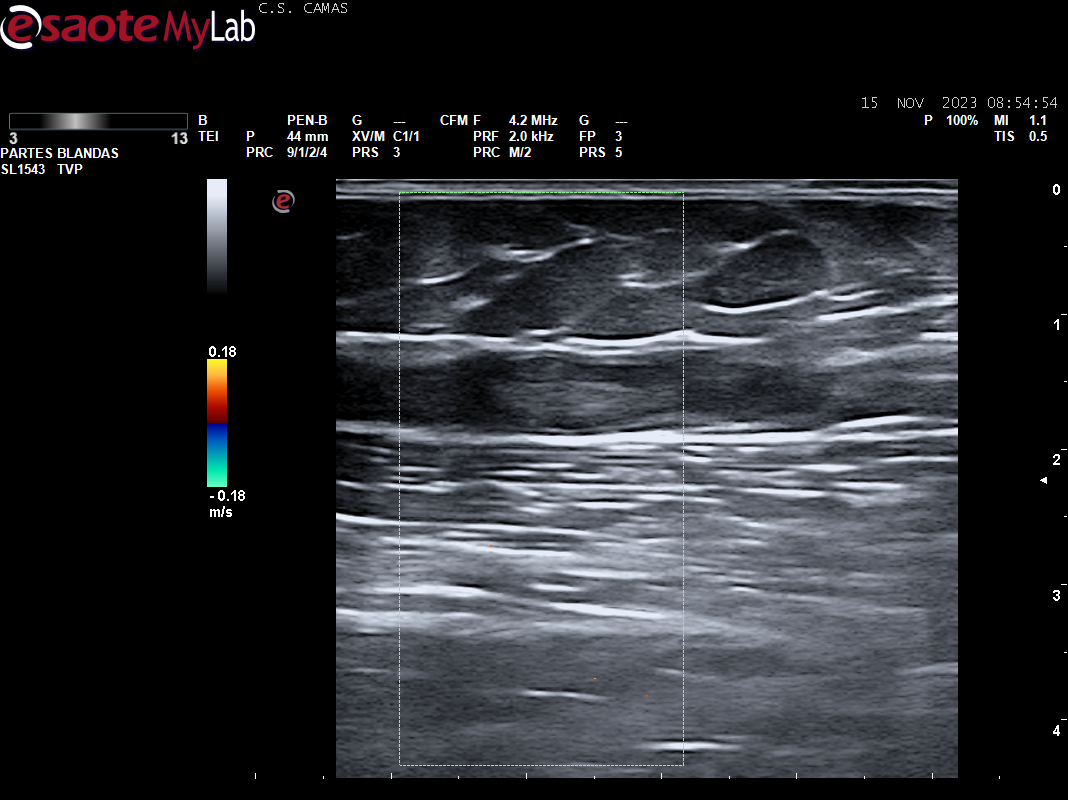

Ecografia vascular cara interna del muslo izq: Trombosis de todo el recorrido de la safena izq con dolor al paso de la sonda por colaterales inferiores que colapsan. Presenta además en zona del cayado de la safena imagen heterogenea sin apreciar la llegada de la safena a la femoral común compatible con arrancamiento de la misma.

Trombosis de todo el recorrido de la safena interna izquierda con tromboflebitis de las colaterales inferiores que concuerda con el diagnóstico hospitalario.